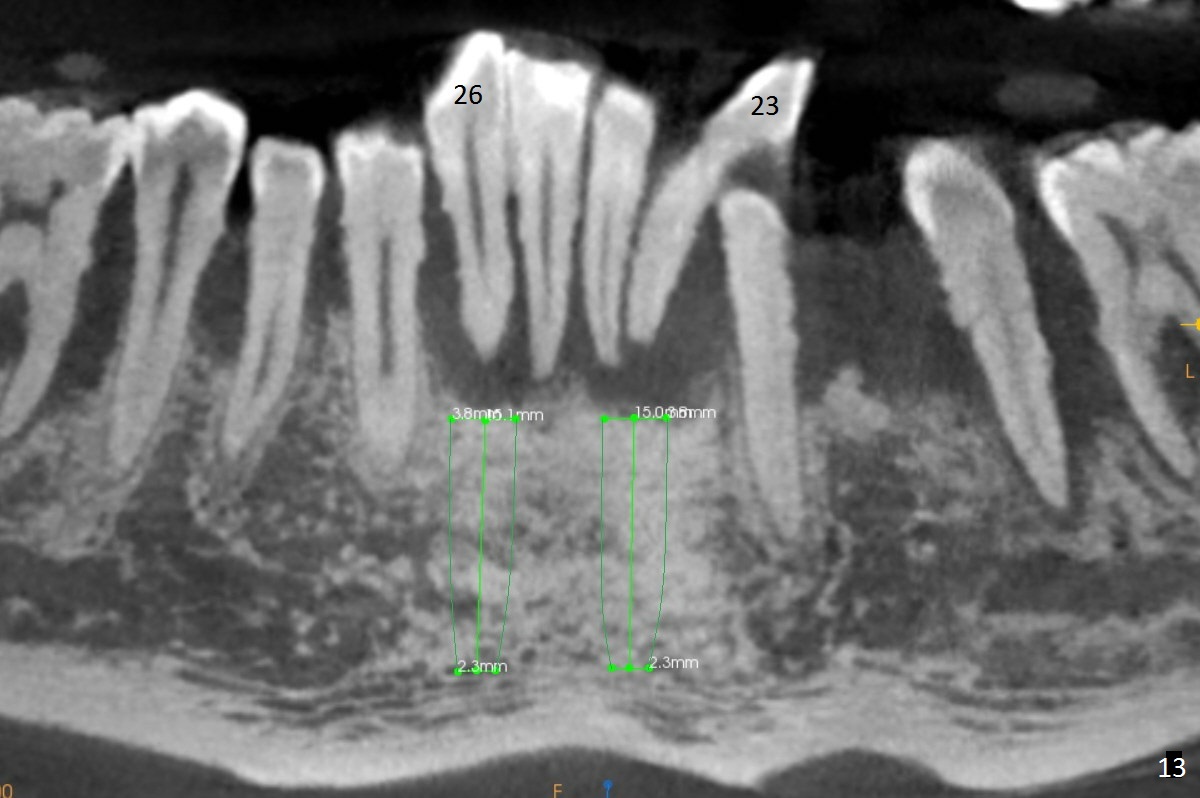

Class II Division II malocclusion (Fig.2,6) will make it difficult to restore #23-26 implant-supported FPD. Although the teeth #7-10 may need to be replaced later (Fig.7,8), enameloplasty will be conducted for #7-10 (Fig.9 white area; Fig.12 black circles (gross reduction)) prior to #23-26 extraction and implant placement (Fig.10). To be flexible in restoration (angulation) and possible future hybrid denture, 2-piece narrow implants will be placed (3.0 or 3.3 mm) instead of 1-piece ones. In fact CBCT shows that the narrowest regular implant (3.8 mm) can be placed in the lower anterior region (Fig.13-15).